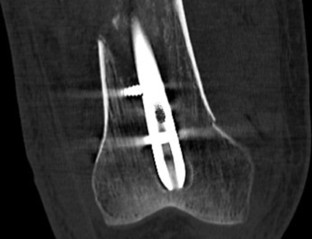

Abb. 1